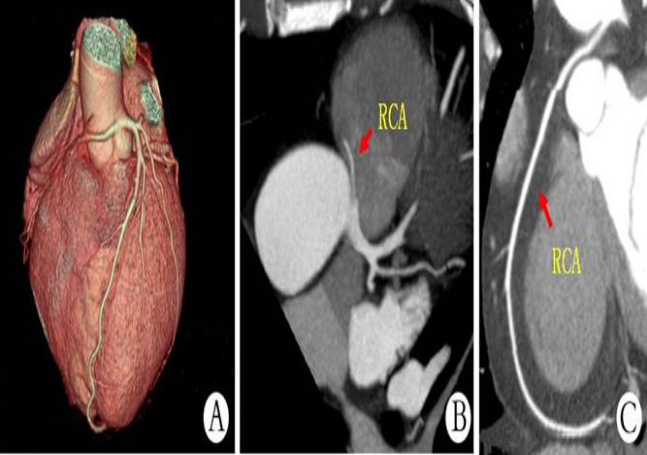

冠狀動脈CTA檢查是一種經(jīng)靜脈注射造影劑后利用螺旋CT掃描再經(jīng)過計算機處理重建得出的心臟冠脈成像的一種影像學(xué)檢查方法。冠脈CTA可用于觀察冠狀動脈有無斑塊形成,判斷血管狹窄情況,了解血管有無變異以及對與冠脈支架和搭橋術(shù)后進行定期隨訪,冠脈CTA優(yōu)勢在于;無創(chuàng),簡便易行,無需住院,價格相對低廉,多角度觀察血管剖面。

今天我就和大家介紹一下我們影像科的一項有關(guān)冠心病的檢查技術(shù)冠狀動脈CTA, 現(xiàn)在冠心病是心血管病常見病之一,又是心血管病的主要死因,其中超過一般的冠狀動脈事件發(fā)生在沒有癥狀的人群,因此,早期診斷冠心病具有重要意義,而冠狀動脈CTA是早期篩查冠心病的首選。冠心病的危險因子包括:遺傳,高血壓,高血脂,吸煙,肥胖,缺少活動,焦慮抑郁等。已過40歲有以上危險因素的人群應(yīng)進行冠脈CTA檢查。